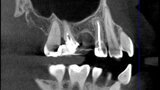

Use of 3D technology in the diagnosis and treatment of endodontic disease